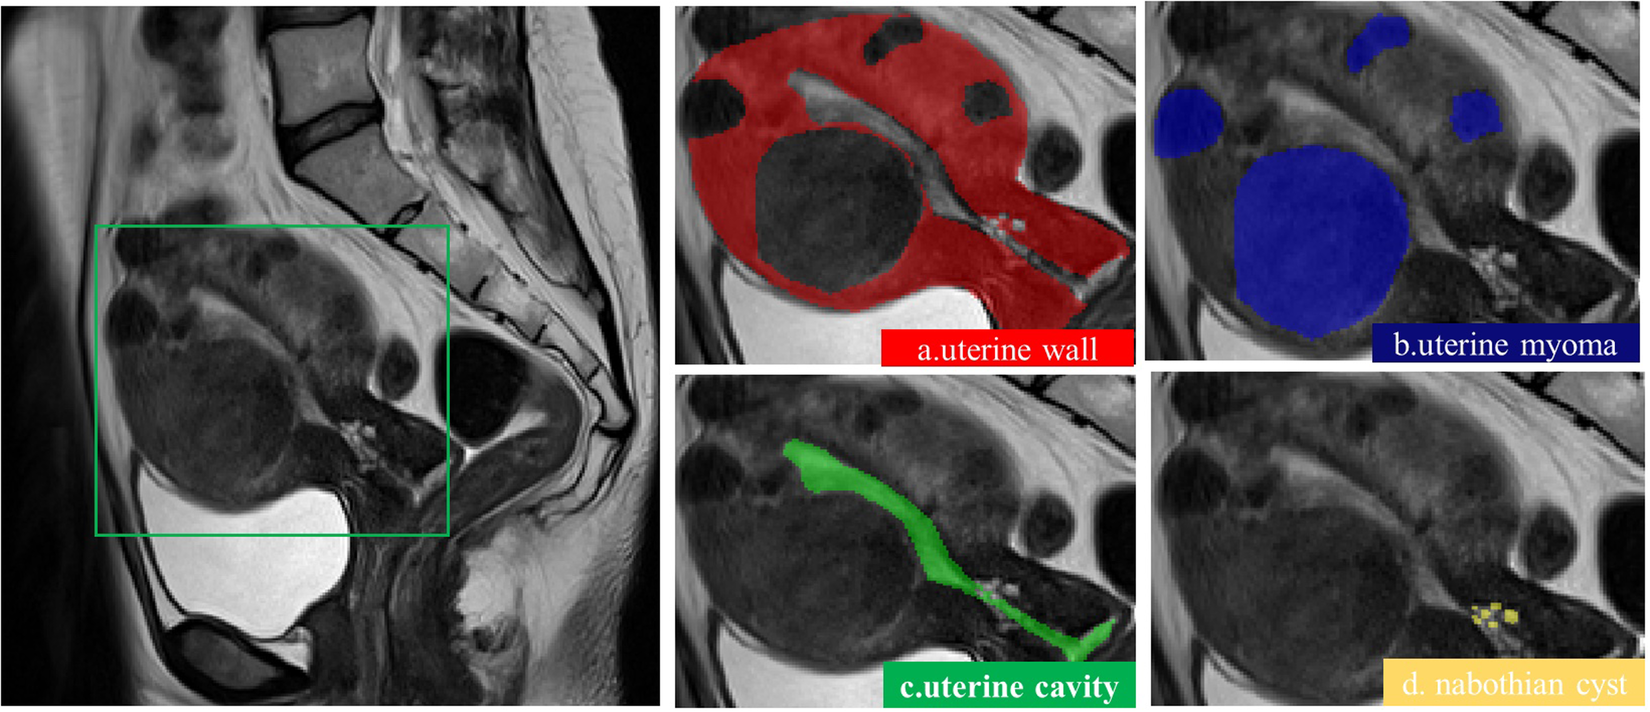

Fig. 3

A description of the uterus. Image blocks are shown from left to right.